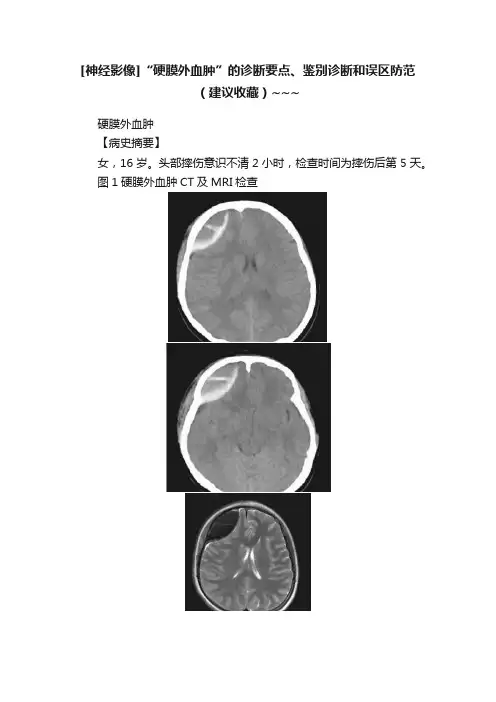

[神经影像]“硬膜外血肿”的诊断要点、鉴别诊断和误区防范(建议收藏)~~~硬膜外血肿【病史摘要】女,16岁。

头部摔伤意识不清2小时,检查时间为摔伤后第5天。

图1硬膜外血肿CT及MRI检查【影像所见】图1A、B,CT显示右侧额部双凸透镜形病变,周边呈高密度,中心呈等密度,其内可见高密度条形影。

图1C、D,横轴面T1WI、T1WI显示右侧额部双凸透镜形异常信号,呈短T2长T1信号,其内可见分隔,周围可见短T1信号。

右侧额叶皮质呈受压改变。

图1E,DWI示病变呈低信号。

图1F,增强扫描病变周边呈异常强化。

【诊断和分析】本病例诊断为右侧额部硬膜外血肿。

影像学诊断要点:①血肿位于硬脑膜和颅骨之间,颞、顶区是最常见的位置,95%位于幕上;②表现为双凸透镜形状;③可以跨过硬膜附着处,但不跨颅缝;④CT12/3表现为均匀一致的高密度,1/3表现为高、低混杂密度,表明活动性出血;⑤MRI,颅骨和硬脑膜之间的双凸透镜形的异常信号,移位的硬脑膜表现为低信号线,位于血肿和脑组织之间,根据出血时间不同血肿信号有所不同;⑥邻近脑组织受压移位,严重者可发生脑疝。

【鉴别诊断和误区防范】本病一般病史明确,诊断比较容易。

【检查方法及选择】本病的主要检查方法是CT和MRI。

CT不仅可以清晰地显示骨折的情况,对于急性期血肿的显示也较清晰。

MRI可以监测血肿的演变过程,因此CT与MRI联合使用,有助于观察病变的发生、发展过程。

【临床病理和随访】硬膜外血肿多由骨折导致脑膜中动脉或静脉窦撕裂造成,见于85%~95%的硬膜外血肿患者,不伴有骨折者少见。

偶尔硬膜外血肿可以不需手术治疗而自行吸收,可能是由于血肿通过骨折处进入帽状腱膜下的软组织。

【评述】由于10%~30%的硬膜外血肿是迟发的,一般在外伤后24~48小时内出现,在受伤当时CT及MRI检查未见异常,因此对于有症状的患者一定要注意复查。